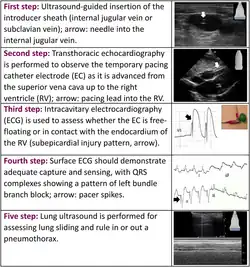

Passos

- O primeiro passo é colocar um introdutor de bainha[1]. Isso geralmente é feito na veia jugular interna direita[5].

- Para verificar o balão no aparelho, encha com 1,5 ml de ar e depois esvazie[5].

- Uma manga estéril é fixada ao cubo da bainha[5].

- Insira o dispositivo cerca de 20 cm (até as 2 linhas pretas) através do cubo e da manga com a bobina da ponta voltada para a esquerda da pessoa[5].

- Conecte o dispositivo ao gerador de energia e ligue o gerador[5]. O eletrodo positivo vai para o terminal positivo do conector e o eletrodo negativo vai para o terminal negativo do conector[2].

- Ajuste o gerador para 80 BPM e a saída para 20 mA[5][2]. A sensibilidade deve ser definida como assíncrona e no menor número de sensibilidade[2].

- Encha o balão e avance o marcapasso para o ventrículo direito[5]. Isso aparecerá como picos de marcapasso e um amplo complexo QRS no monitor[5].

- Ajuste a saída do gerador para o menor mA efetivo[5]. Diminua a taxa para 60 BPM[2]. A sensibilidade também pode ser aumentada[2].

- Desinfle o balão e prenda a manga e a bainha no lugar[5].

O dispositivo de estimulação também pode ser avançado através da veia sob orientação de eletrocardiografia (ECG) ou ultrassom [1][5]. Antes de puxar o dispositivo para trás, certifique-se de que o balão esteja vazio[2].